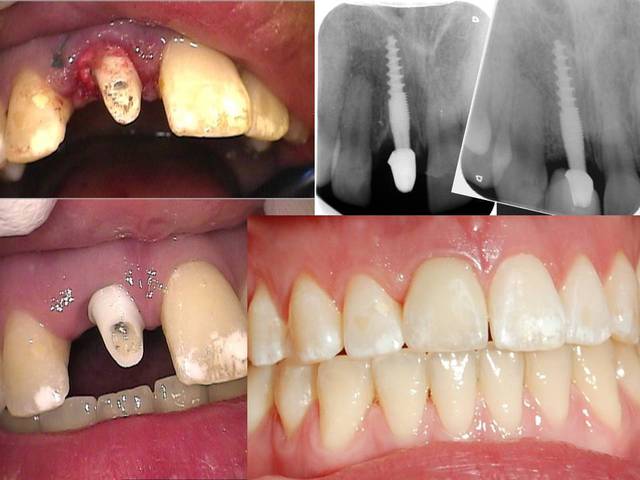

Oui tu as bien raison :-) Ci joint quelques photos en rapport avec ta question ....

20120327 154220 azpc5k - Eugenol

20120327 152704 psin9r - Eugenol

11 immidiat implantation ajhuew - Eugenol

Les nombreux cas déjà postés montrent que cela fonctionne et au long terme (radios après 10 ans), et que l implantologie peut être "démystifier" ( si le mot existe...) :-)